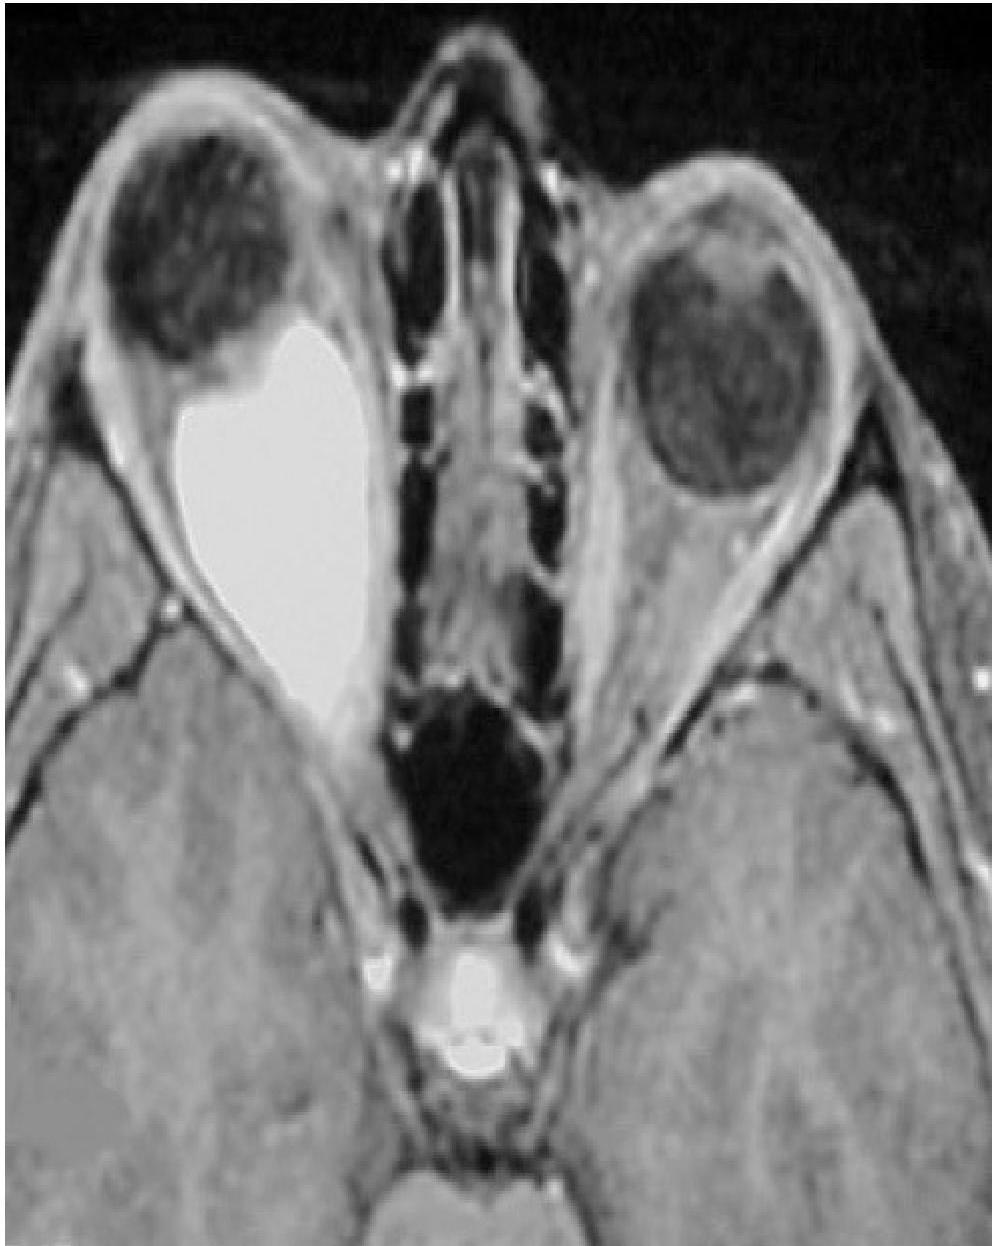

6. Optic Glioma

- The most frequently observed CNS tumor in NF1.